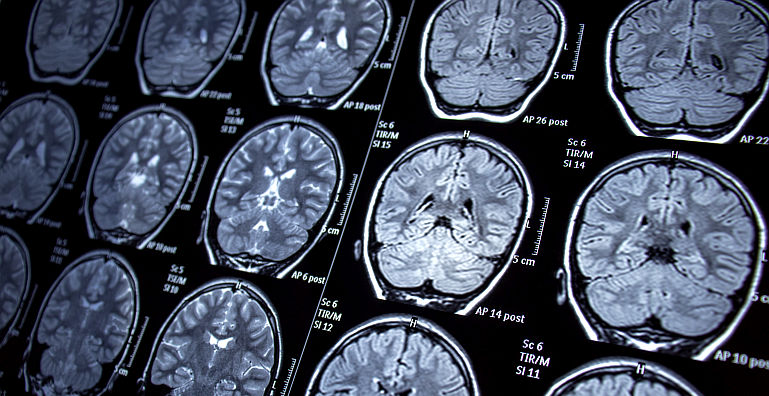

Pacienta cu hemoragie cerebrala si episoade halucinatorii este recuperata de #SuperMedici Pacienta cu hemoragie cerebrala si episoade halucinatorii este recuperata de #SuperMedici

Urmare a unui accident vascular care a adus-o intr-o stare usor confuza, agitata si in cautarea unor usi care nu exista, doamna P., in varsta de 74 de ani, a avut norocul sa ajunga in cel mai bun...